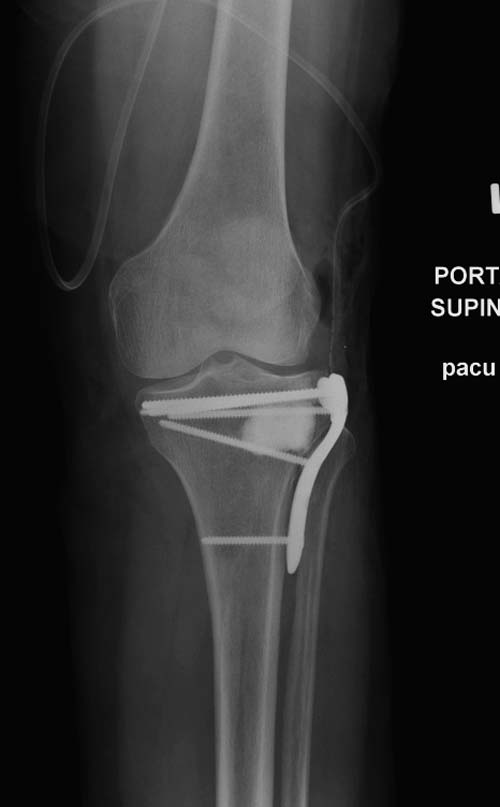

Устранение импрессии, костная аутопластика, остеосинтез опорной пластиной

задний кортекс не повреждён. Подойдёт рафтинговая пластина.

Учитывая, что у пациента молодой возраст(судя по рентгенограммам,абсолютно показано восстановление суставной линии: подменисковый доступ,подъём импренированной части мыщелка, костная аутопластика, остеосинтез, решение вопроса с мениском (шов либо парциальная резекция)).

Как подсказывают, можно с противоположной стороны приподнять сустав и заполнить костный дефект. Параллельные винты создадут достаточную опору, но иногда buttress plate за счет диафиза создает дополнительную стабильность. Структуральный материал для профилактики от раннего коллапса, и пластическим материалом служит более твердый синтетический материал (Osteoset DBM) или аутокость.